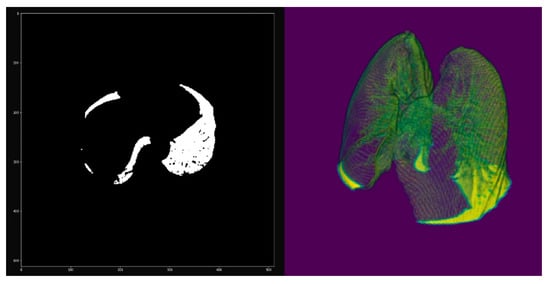

3.1. From dicom to 3D Models with Automatic Segmentation

3.2. Results Visualization